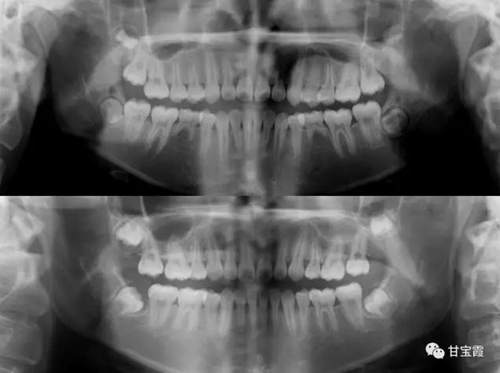

于是我們決定拔出滯留的下頜乳牙和上頜的兩顆第一雙尖牙。

3.jpg

矯正中排齊并內(nèi)收上下前牙,同時也適當(dāng)?shù)那耙屏讼骂M后牙,關(guān)閉了所有的拔牙間隙,患者長大以后也不必要再鑲牙了。

4.jpg

下面這兩張X片子就是矯正前后的對比,看不出下頜缺牙

5.jpg